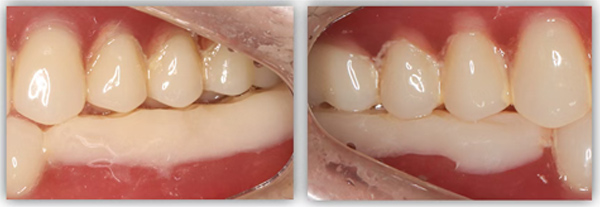

我決定做難但正確的事情。種植手術完成后,我讓患者戴上了樹脂義齒重建咬合,讓他通過日常的咀嚼,在原本平整的下牙義齒上慢慢形成新的尖窩對應關系。前后花了半年時間,才達到穩定且可重復的咬合狀態。這時候,再制作第二幅臨時義齒,也就是有解剖牙尖和尖窩交錯關系的臨時牙,讓患者再次適應咬合3個月。最后,我把患者適應并且滿意的咬合關系轉移到他的最終牙冠上,完成了修復治療。

這位患者不到60歲,但由于后牙全部缺失多年,殘留的前牙已松動且上下無法接觸,他基本沒辦法正常咀嚼,人非常消瘦。完成治療后我跟蹤了這個病例一年,從前后對比照片可以看出,能正常吃東西后他的臉上漸漸也有肉了。